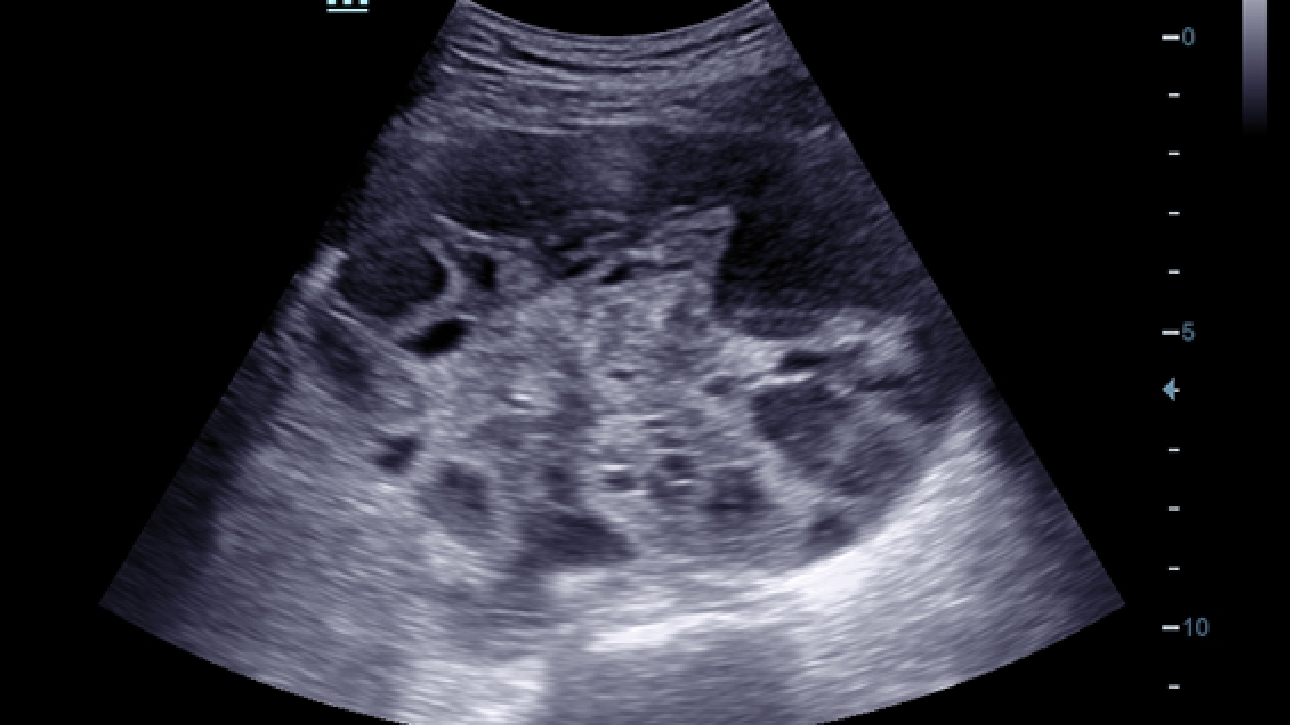

X-Insight, daha geli?mi? g?rĂŒntĂŒler elde etmek i?in kapsaml? bir ??zĂŒmdĂŒr.

Mindrayâin yeni ??zĂŒmĂŒ, geli?en en yeni ultrason teknolojileri ile birlikte, mĂŒ?terilerin g?rĂŒ?lerini klinik gerekliliklerle tam anlam?yla birle?tiren bir ??zĂŒmdĂŒr. Taptaze bir ruhla, gelece?e odaklanarak ve s?n?rs?zl???n pe?inde ko?arak, artan ?l?eklenebilirlikte sĂŒrekli olarak geli?en bir ??zĂŒmdĂŒr.

?ok y?nlĂŒ bir partner olarak, X-Insight'l? DC-60 Exp, her y?nĂŒyle gĂŒnlĂŒk klinik uygulamay? kolayl?kla ve belirsizlik olmadan y?netmenize yard?mc? olacak kapsaml? bir ??zĂŒm sunar.

MĂŒ?teri gereksinimlerine y?nelik g?rĂŒ?ler temelinde, X-Insight'l? DC-60 Exp, eXpress Clarity, eXceptional Intelligence ve eXceeding Experience ile gĂŒ?lendirilerek, hassas g?rĂŒntĂŒlemeyle yĂŒksek verimlilik sa?layacak ?ekilde tasarlanm??t?r.